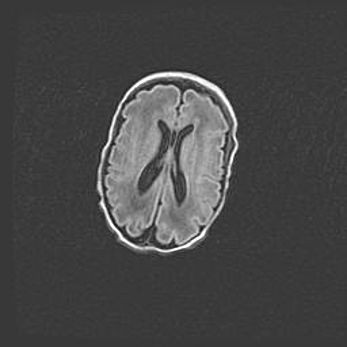

Мальформация Денди-Уокера. Киста задней черепной ямки.

Агенезия мозолистого тела.

Возраст: 2,5 месяца

Вес: 2420 г

Пол: женский

Окружность головы: 37 см

Срок гестации: 32 недели

Мальформация Денди—Уокера — редкий вид патологии ЦНС, представляющий собой врожденный порок развития каудального отдела ствола и червя мозжечка, ведущий к неполному раскрытию срединной (Мажанди) и латеральных (Лушка) апертур IV желудочка мозга. Для этогно синдрома характерна триада симптомов: гипотрофия червя мозжечка и/или полушарий мозжечка, кисты задней черепной ямки, гидроцефалия различной степени. В 70% случаев порок сочетается и с другими аномалиями головного мозга, в частности с агенезией мозолистого тела.